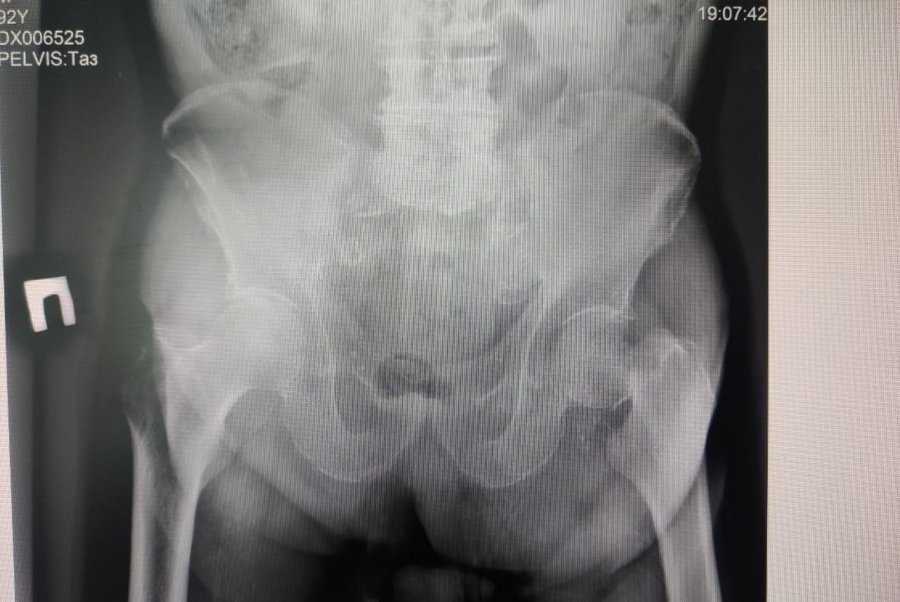

Врачи Каширской ЦРБ в очередной раз доказали, что переломы в пожилом возрасте не приговор. Как сообщили в учреждении, в травматологическое отделение Хирургического корпуса поступил 92-летний пациент Роман Владимирович (инициалы изменены) с жалобами на боль в бедре после падения. При осмотре и рентгенологическом обследовании ему диагностировали перелом шейки бедра. Это серьезное состояние, особенно в таком возрасте, требует квалифицированного медицинского вмешательства. Благодаря профессиональным навыкам и опыту наших врачей и медицинского персонала, была проведена операция - эндопротезирование тазобедренного сустава. Этот метод вмешательства, как уточняется, позволяет восстановить функциональность тазобедренного сустава и вернуть пациенту возможность нормальной ходьбы.

«После перелома шейки бедра человек зачастую оказывается прикован к постели, и это грозит опасными для здоровья осложнениями, которые в конечном счёте приводят к смерти. Поэтому главной нашей задачей было как можно раньше вернуть пациента к физической активности. Мы выполнили эндопротезирование тазобедренного сустава. На операцию ушло не более одного часа», – рассказал заведующий травматологическим отделением Константин Смирнов.